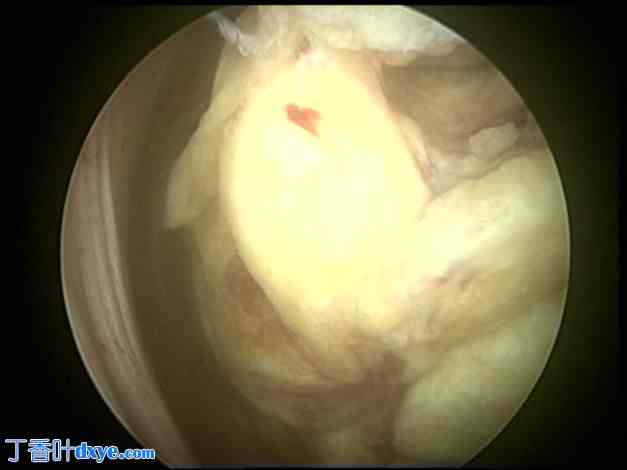

图3. 宫腔镜检查显示,肌瘤排出宫腔,呈萎缩性外观。